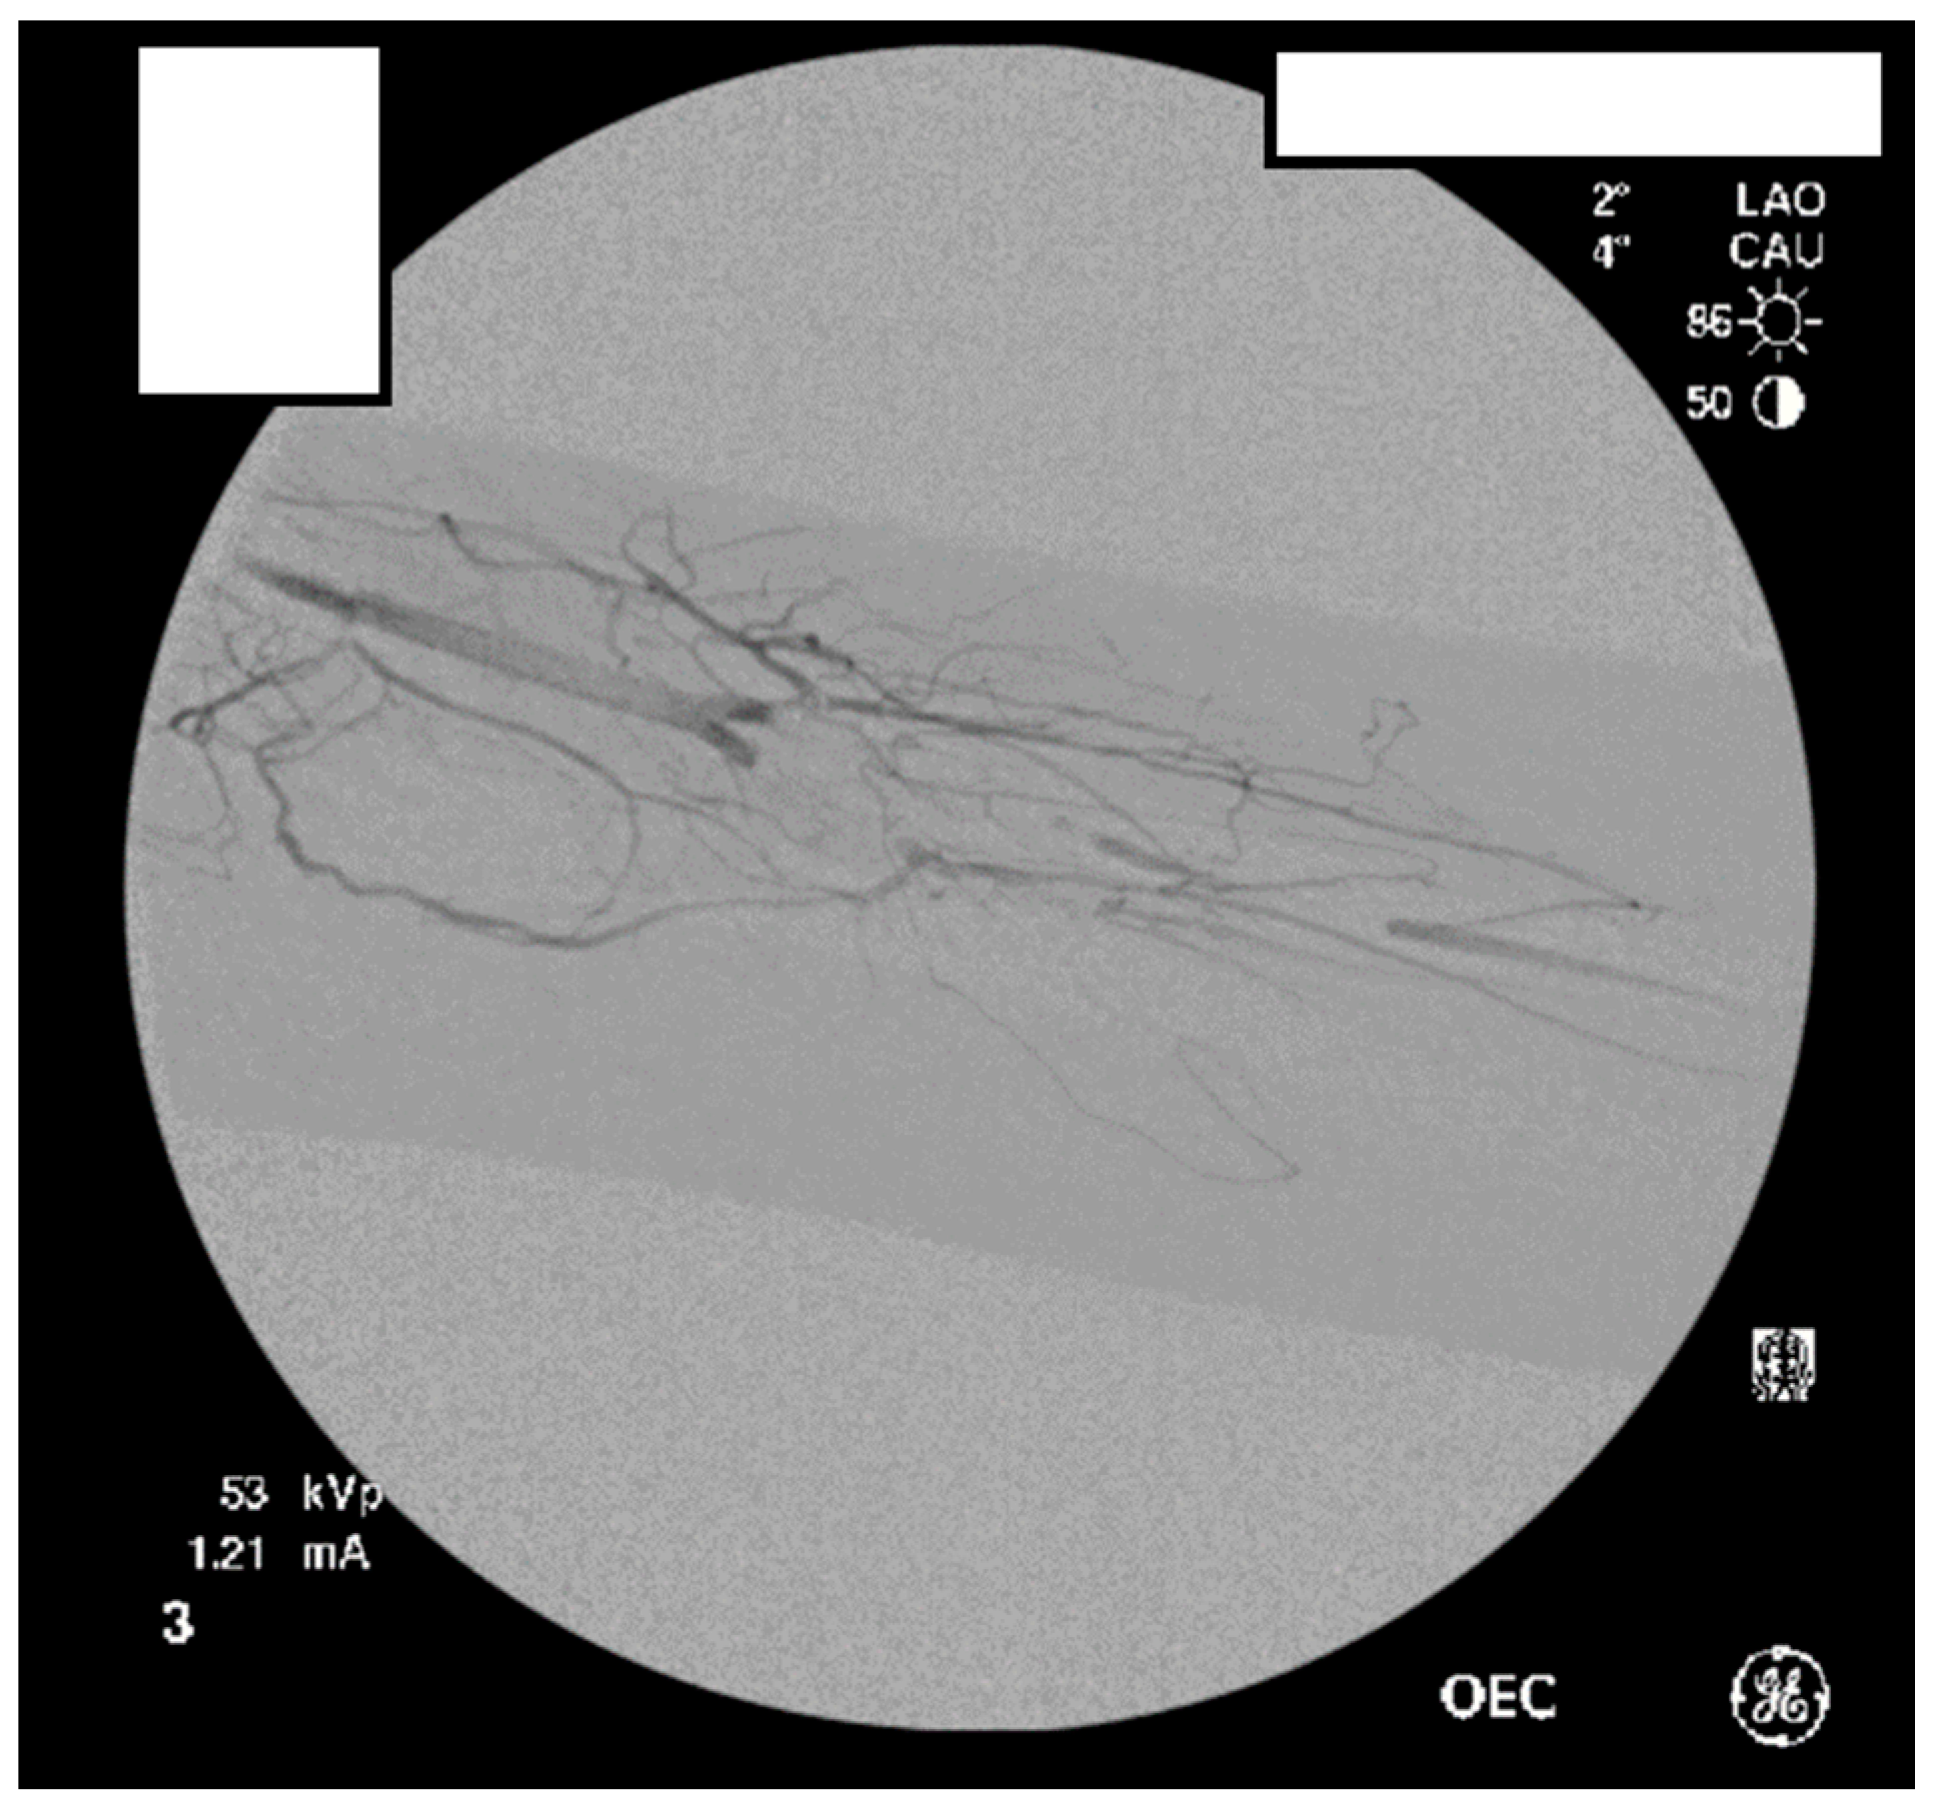

Figure 7.

Left subclavian arteriography demonstrating a thrombosed brachial artery at the mid-humeral level and extensive collateralization proximally.